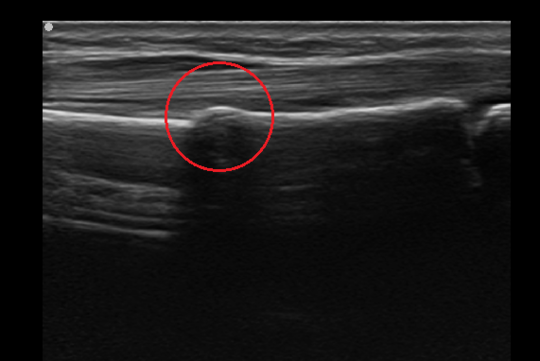

エコー画像では赤丸印のように白い骨のラインが膨隆して観察することができます。

エコー画像(赤丸が骨折部)